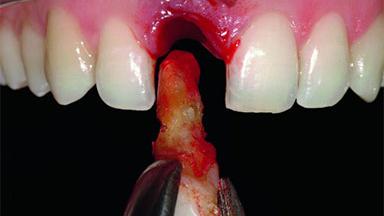

Replacement of an Upper Right Central Incisor with Root Resorption: Ridge Preservation, Delayed Placement of an NC Bone Level Roxolid Implant

A 32-year-old female Caucasian patient with a compromised maxillary right central incisor was referred to us by a general dentist. Her chief complaints were discomfort and mobility of tooth 11 with unsatisfactory esthetics due to discoloration. The patient reported a previous trauma, some years earlier, as the origin of pathology on the afflicted tooth. Anamnesis was negative for any other dental or periodontal pathology in the remaining dentition. The patient did not take any medication and reported to be a light smoker (5–10 cigs/day). She had high esthetic expectations of her treatment. The extraoral examination revealed a high smile line with full exposure of her maxillary teeth and surrounding soft tissue in the area between the second premolars.

| Bone Volume | Deficient horizontally, requiring prior grafting |